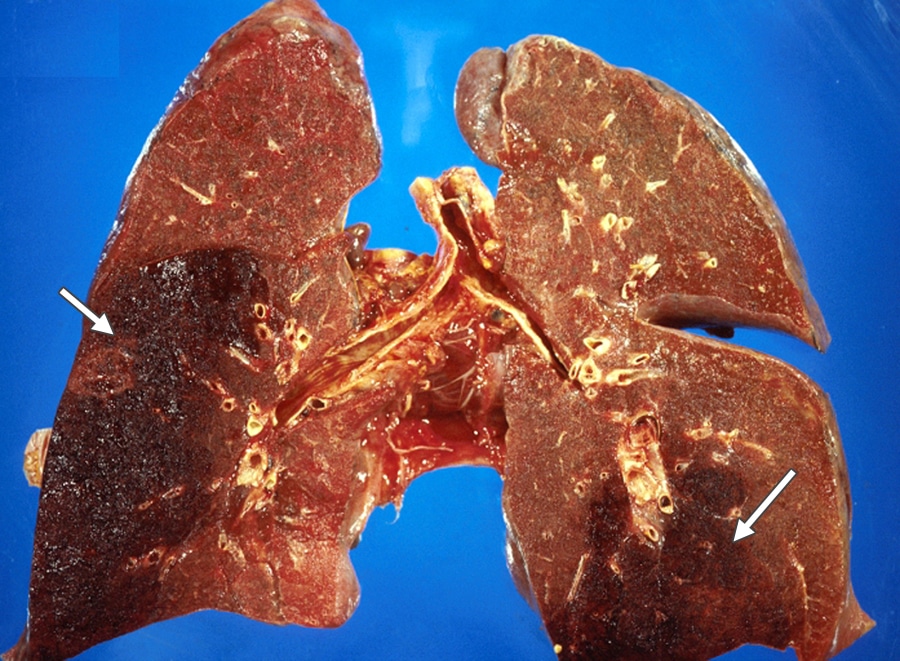

Инфаркт лёгких — серьёзное осложнение лёгочной эмболии, вызвал отмирание тканей